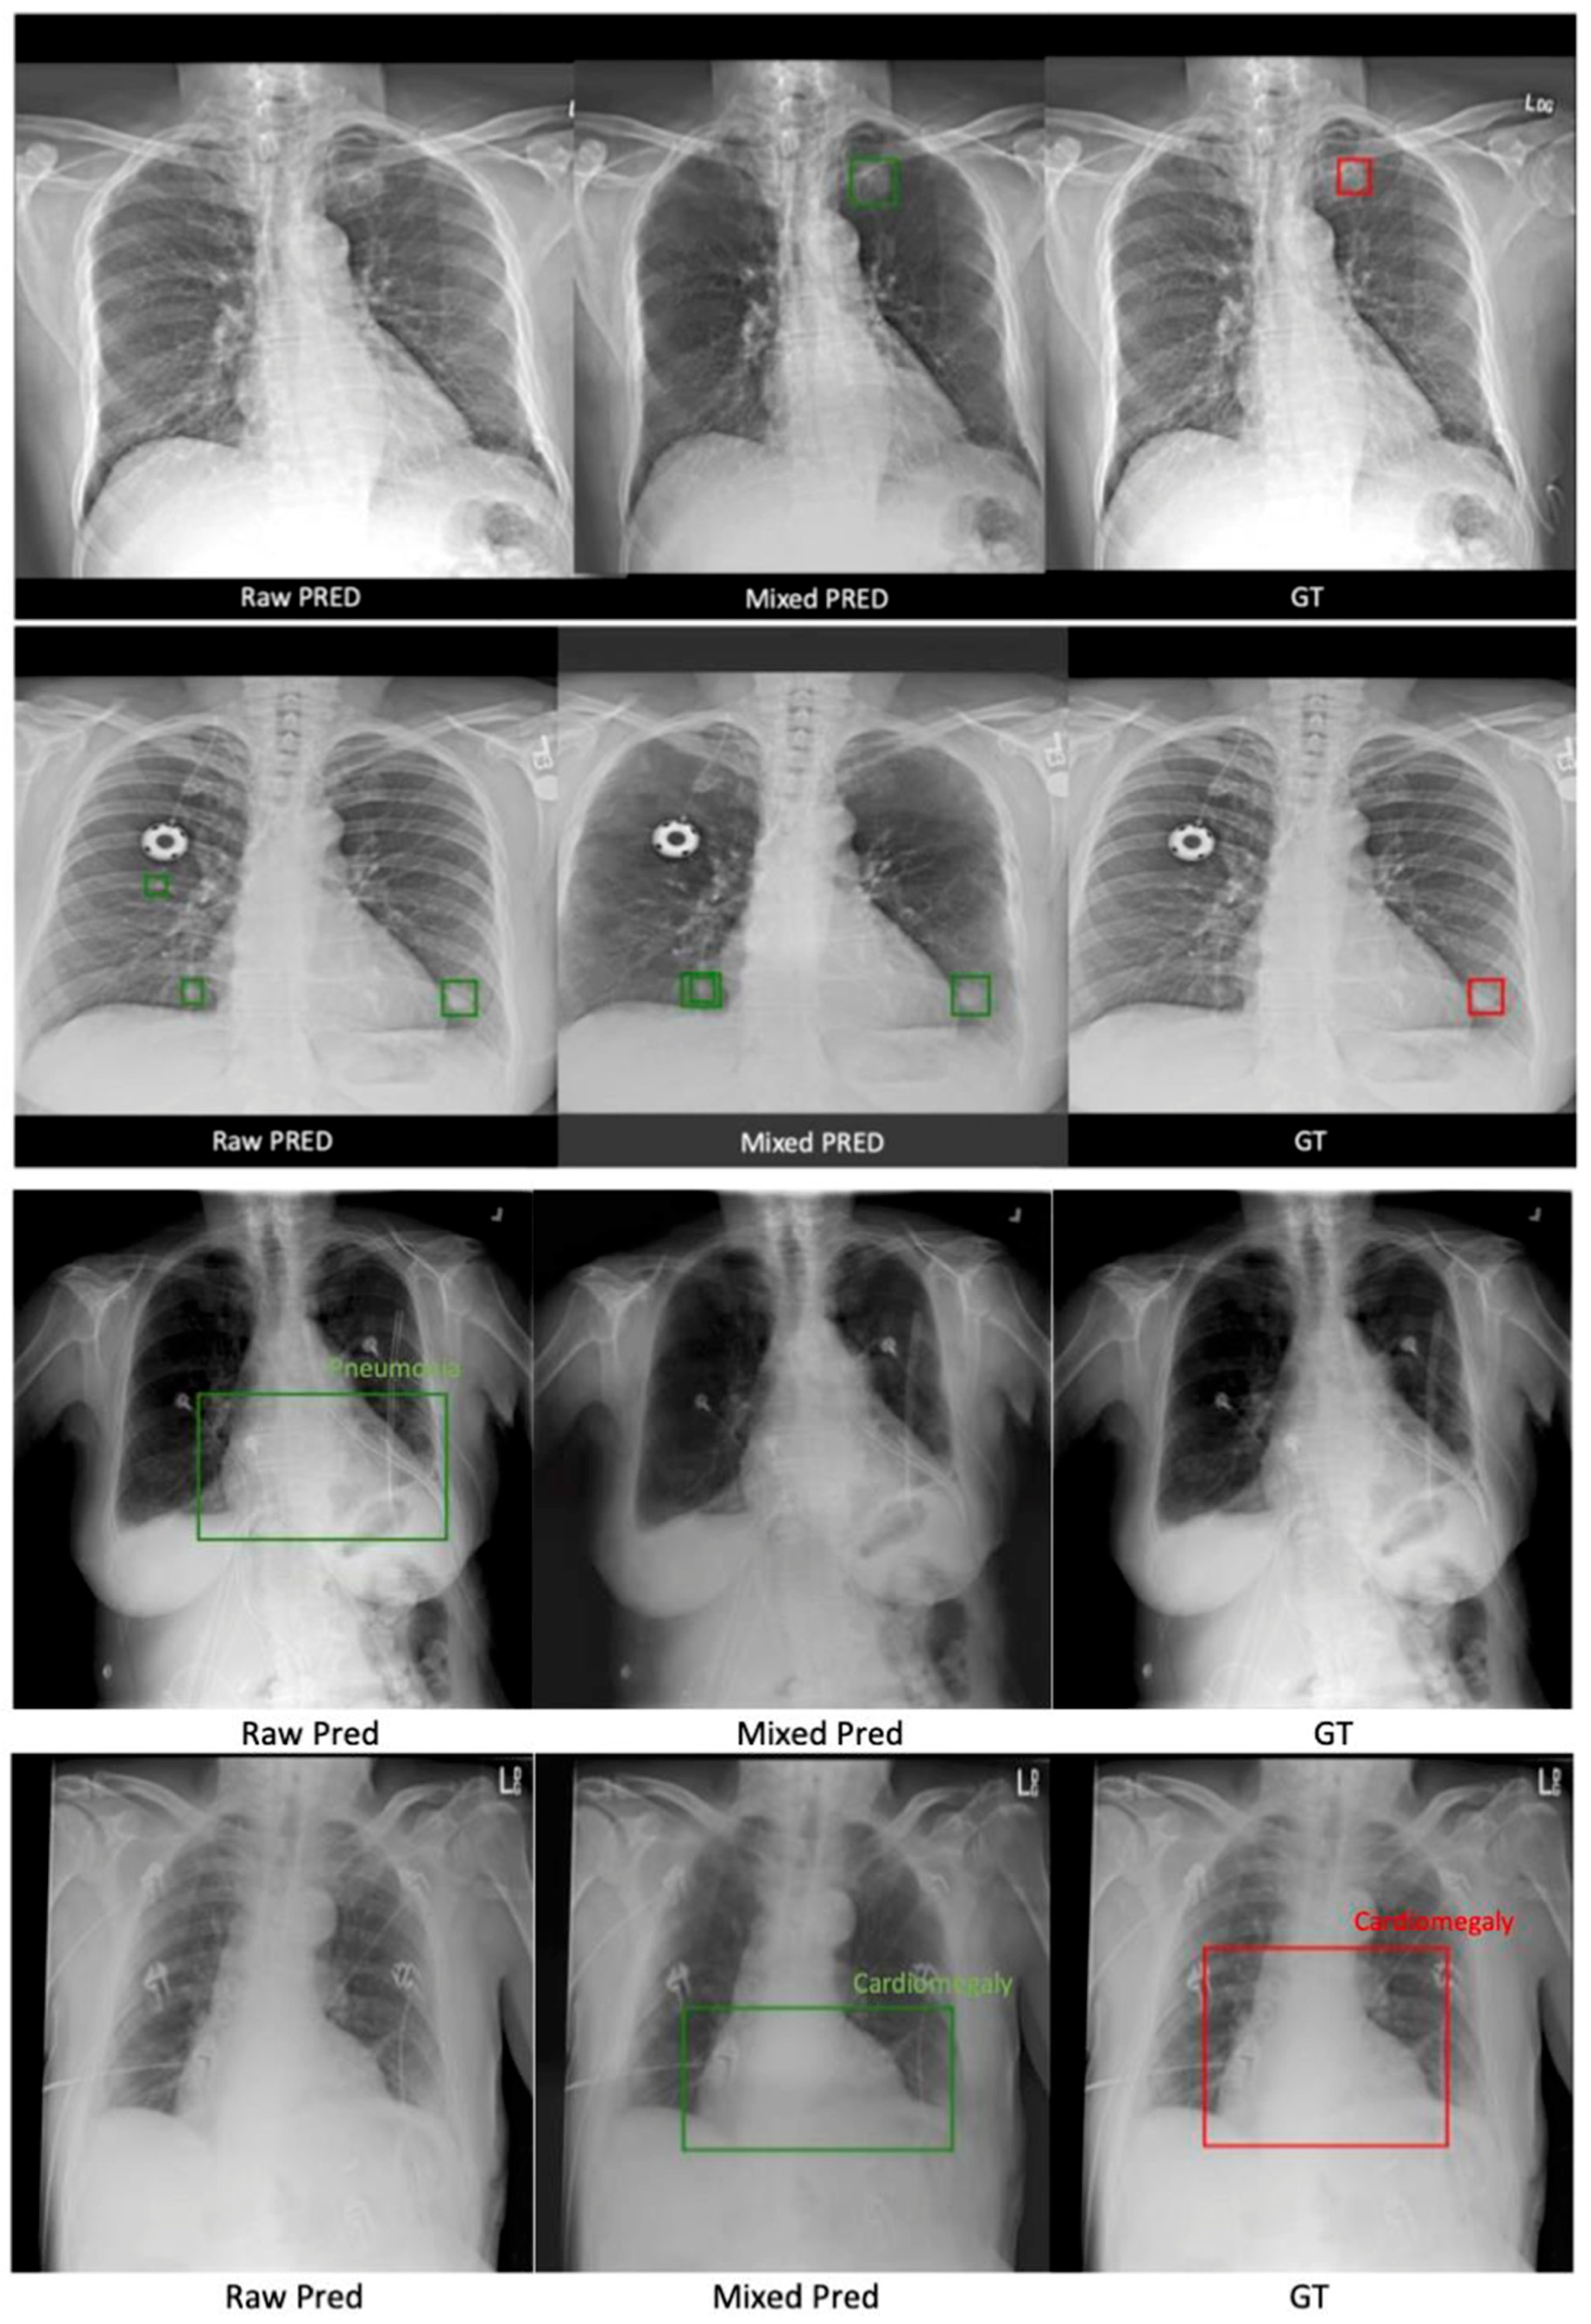

3.2.2. ChestX-ray14 Classification and Localization

4. Discussion